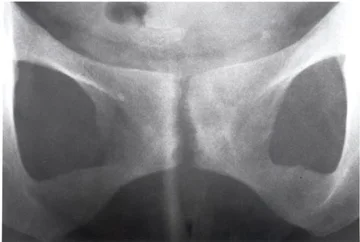

Figure 1: Osteitis Pubis can cause an inflammatory reaction at the joint at the front of the pelvis

Osteitis pubis is an inflammatory condition that affects the Symphysis Pubis (the joint between the pubic bones-see image to right). Osteitis Pubis is most common in sports where a large shearing force goes across the Pubic Symphysis. This occurs during kicking activities, running and changing directions and therefore is relatively prevalent in the football codes. The excessive forces overstrain the Pubic Symphysis causing a painful inflammatory response which if not managed early can subsequently lead to an erosion process affecting joint margins of the Sympysis Pubis.